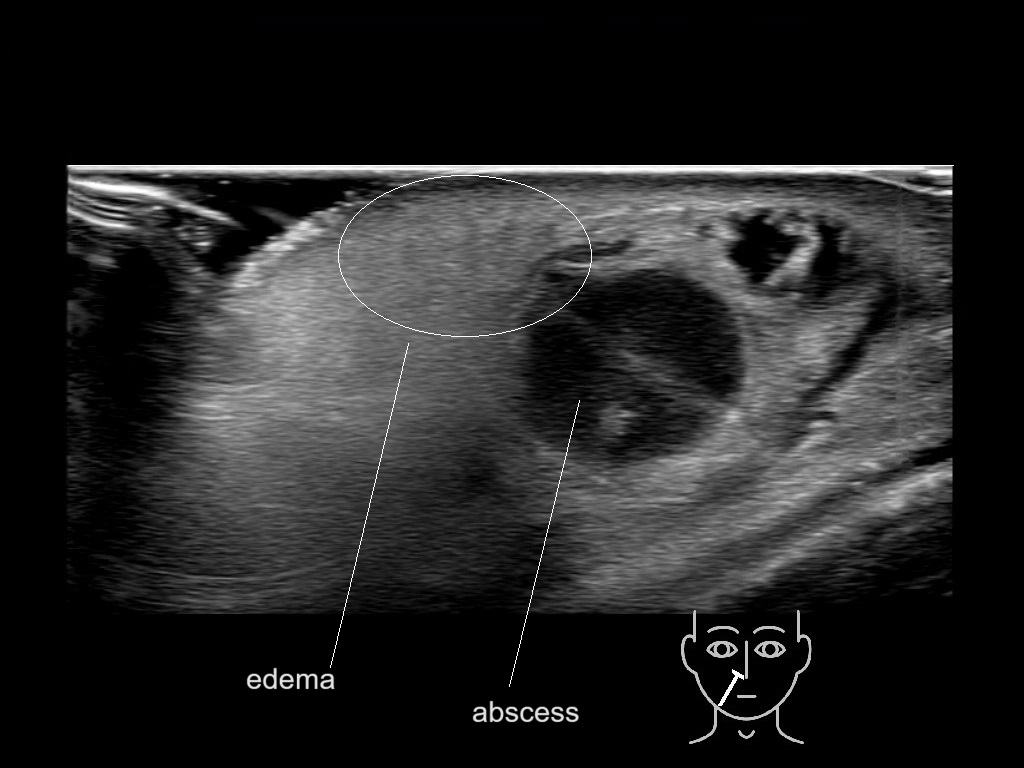

With ultrasound signs of inflammation can be visualized. Edema can be seen as a hyperechoic appearance of the subcutaneous fat, sometimes separated by hypoechoic fluid filled area’s, known as cobblestone appearance. Increased vascularization (hypervascularity) can be seen on colour Doppler. An abscess will appear as a fluid collection appearing as an irregular hypoechoic area with heterogeneous internal echoes and a thickened wall. Posterior acoustic enhancement can be present, and there is vascularity around but not within the mass. Under ultrasound guidance, abscesses can be managed by needle aspirations (18G) under antibiotic cover.

Study the first image to recognize the different layers. If you are sure about the layers, swipe to the second image to view the answer (if applicable).